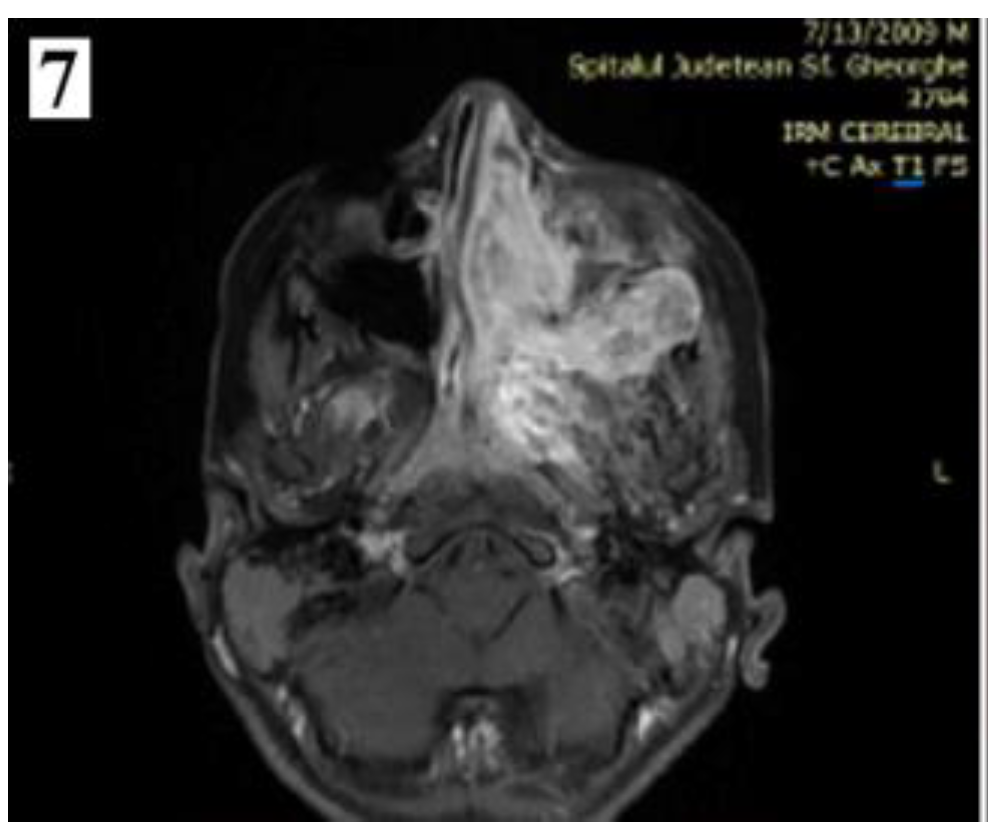

Figure 7.

Preoperative MRI of a stage IIC juvenile angiofibroma. The Holman-Miller sign (the anterior bowing of the posterior maxillary wall) on the CT scan (part 1).

Figure 8.

Preoperative MRI of a stage IIC juvenile angiofibroma. The Holman-Miller sign (the anterior bowing of the posterior maxillary wall) on the CT scan (part 2).

Management of stage IIC cases, with extension into the infratemporal fossa or extension posteriorly to the pterygoid plates, can be done by transnasal approach alone or by a combined approach. Preoperative embolization is mandatory for identifying the vascular feeding source and reducing intraoperative bleeding.